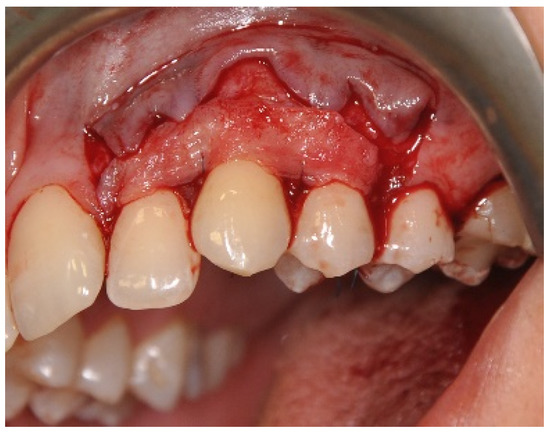

2.3. Surgical Procedures

Surgical Procedure Using Biokol®, the Xenogeneic Lyophilized Collagen Sponge